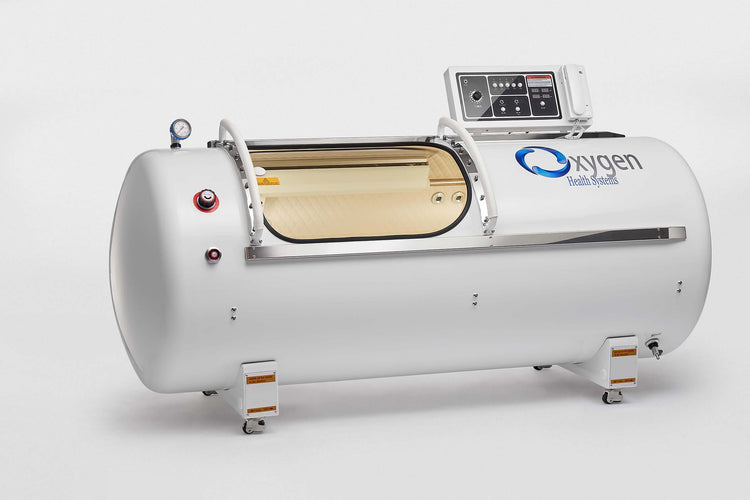

36-Inch Hard Shell Hyperbaric Oxygen Chamber supports 2.0 ATA (100 kPa) pressure and 15 PSI. Built with 2.5 mm thick 304-grade stainless steel and a 10 mm thick polycarbonate window from Bayer Germany. Designed with heavy-duty steel rods and ball-bearing rollers for smooth movement. Features incremental control of pressurization and depressurization, interior and exterior emergency pressure relief valves, interior lighting, and an alarm system. Allows auto-controlled session times up to 2 hours with a timer and offers an optional progressive control feature. Chamber dimensions are 88 inches in length and 36 inches in diameter. Includes a 3-year warranty.